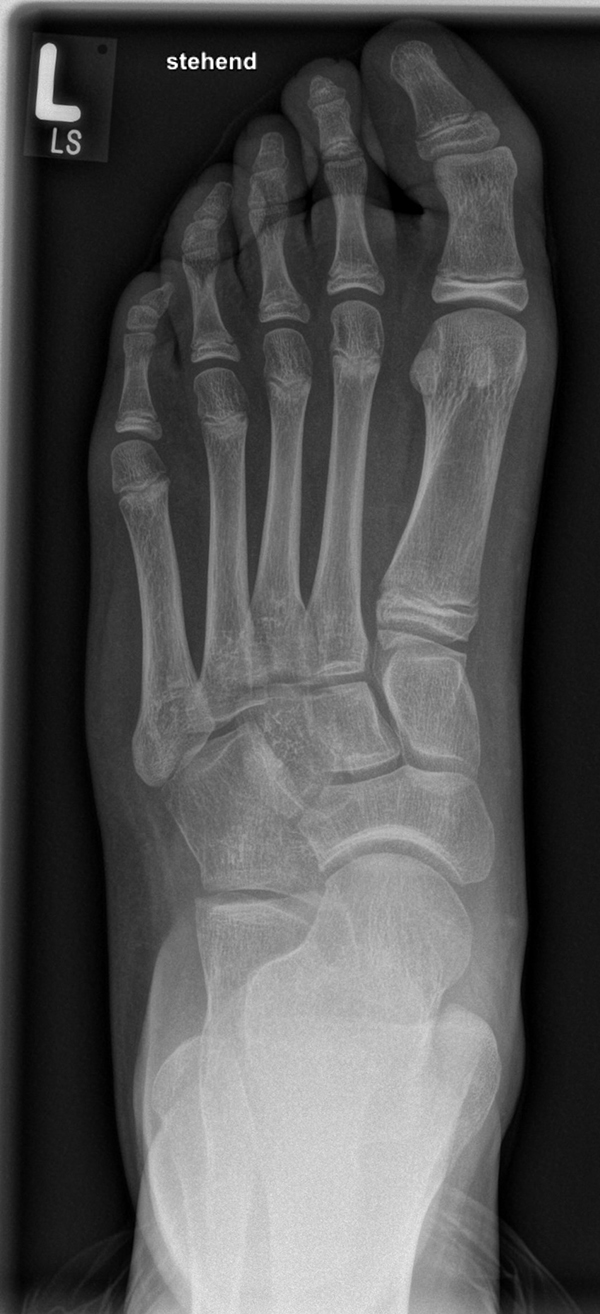

Diagnostisches Vorgehen

Damit die minimalinvasive Fußchirurgie zur Korrektur kindlicher oder jugendlicher Fußdeformitäten erfolgreich angewendet werden kann, erfordert die präoperative Diagnostik Röntgenbilder in drei Ebenen am stehenden Fuß. Röntgenbilder ohne Belastung des Fußes sind nicht zielführend. Im Fall von schweren Rückfußdeformitäten wird das obere Sprunggelenk in die radiologische Diagnostik mit einbezogen in Kombination mit der Rückfußaufnahme unter Belastung („Saltzman View“). Das OSG wird in zwei Ebenen geröntgt. Die streng seitliche Aufnahme des OSG kann bei den komplexen Fußdeformitäten mit der seitlichen Aufnahme des Fußes unter Belastung kombiniert werden. Das reduziert die diagnostische Strahlenbelastung der Kinder.

Indikationen für die beschriebenen Röntgenaufnahmen sind Klumpfußdeformitäten zur Beurteilung eines „flat top talus“ oder neurologische Grunderkrankungen mit varischer Fersenstellung wie zum Beispiel bei HSMN (Hereditäre Sensorische Motorische Neuropathie).